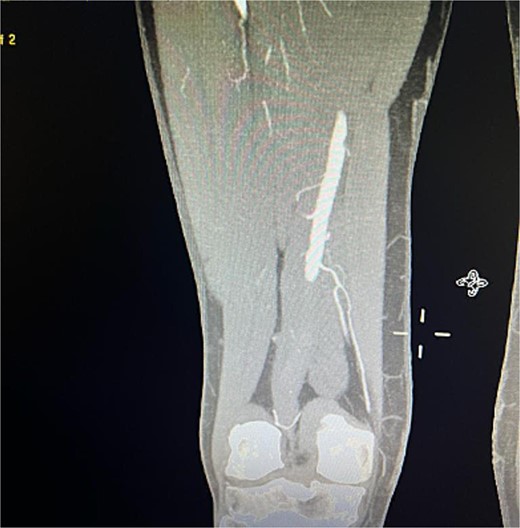

Despite these interventions, the patient experienced further episodes of acute limb ischemia (Fig. 4), leading to thrombolytic therapy a month later. This recurrence prompted a reevaluation of the treatment strategy. We considered extending the graft limb, which would involve sacrificing the hypogastric artery, or using an iliac artery extension with an iliac side branch. We ultimately chose the latter and implanted an E-iliac stent graft (Jotec ISB system) (Fig. 5a and b). Preservation of the hypogastric artery was prioritized, although extending into the external iliac artery would have been a viable alternative. However, the multidisciplinary team decided the preservation of the hypogastric artery would be more appropriate in this patient. The patient was discharged without anticoagulants.

Coronal view of CTA scan showing right femoral artery embolic obstruction